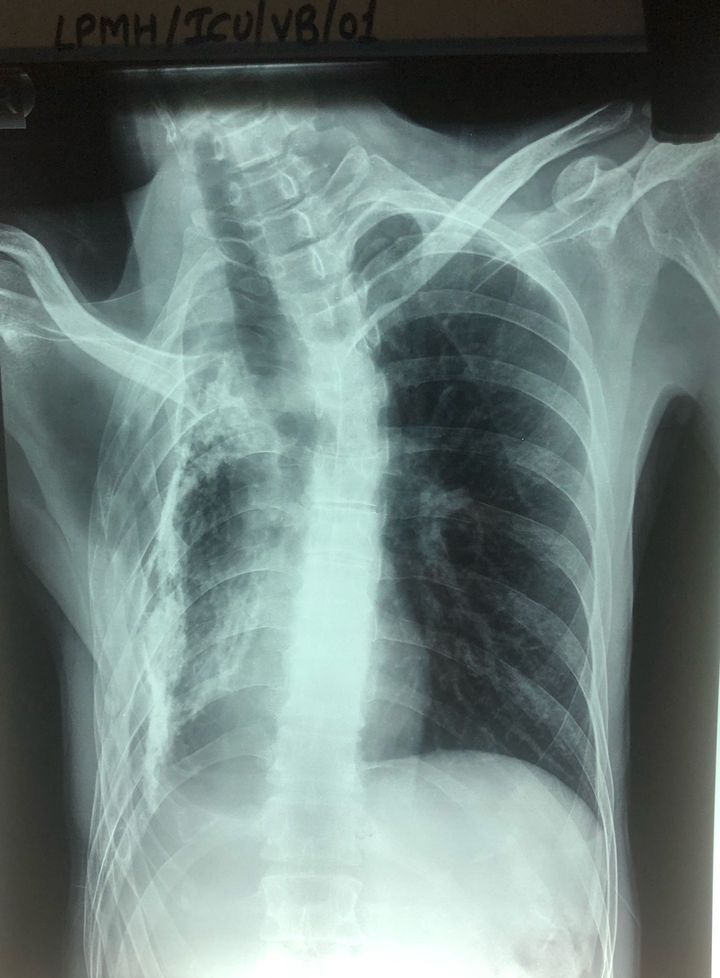

Dignosis...?

Scoliosis

Scoliosis?🤔

Tuberculosis osteomyelitis (gibbus)

Why the lung on one side appears to be flattened?

How it is scoliosis???